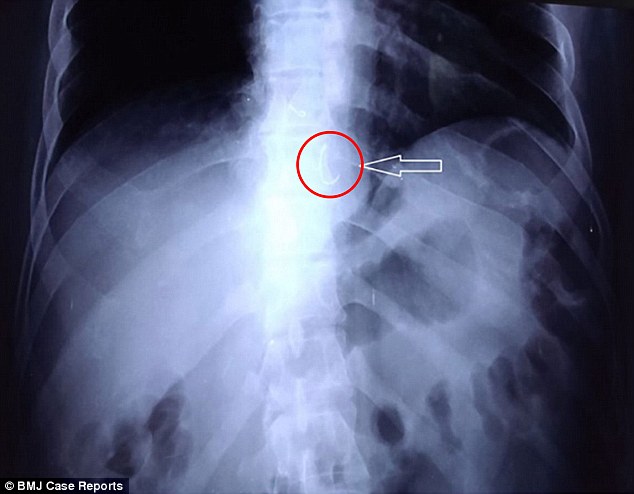

Trakea sendiri memiliki fungsi yang sangat penting bagi saluran pernapasan. Apabila tutup pulpen tertelan maka trakea akan tertutup sehingga pernapasan terganggu. Dengan adanya lubang tersebut maka udara masih bisa masuk ke paru-paru hingga pertolongan pertama diberikan. Itu alasan mengapa lubang pada penutup pulpen ini sangat penting.